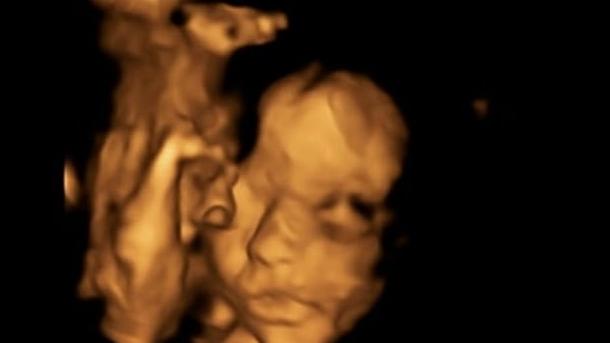

S-a dus să își facă o ecografie în cea de-a douăzecea săptămână de sarcină, iar medicii au sfătuit-o că ar trebui să renunțe la copil, pentru că micuțul avea ruptură de coloană.

Bethan Simpson, 26 de ani din Burnham, Essex, a refuzat însă să facă avort, în schimb a optat pentru o operație revoluționară.

Copilul a fost operat în burtica mamei, iar intervenția a reușit. Acum, Bethan urmează să devină mamă a unei fetițe în luna aprilie, scrie Daily Mail.